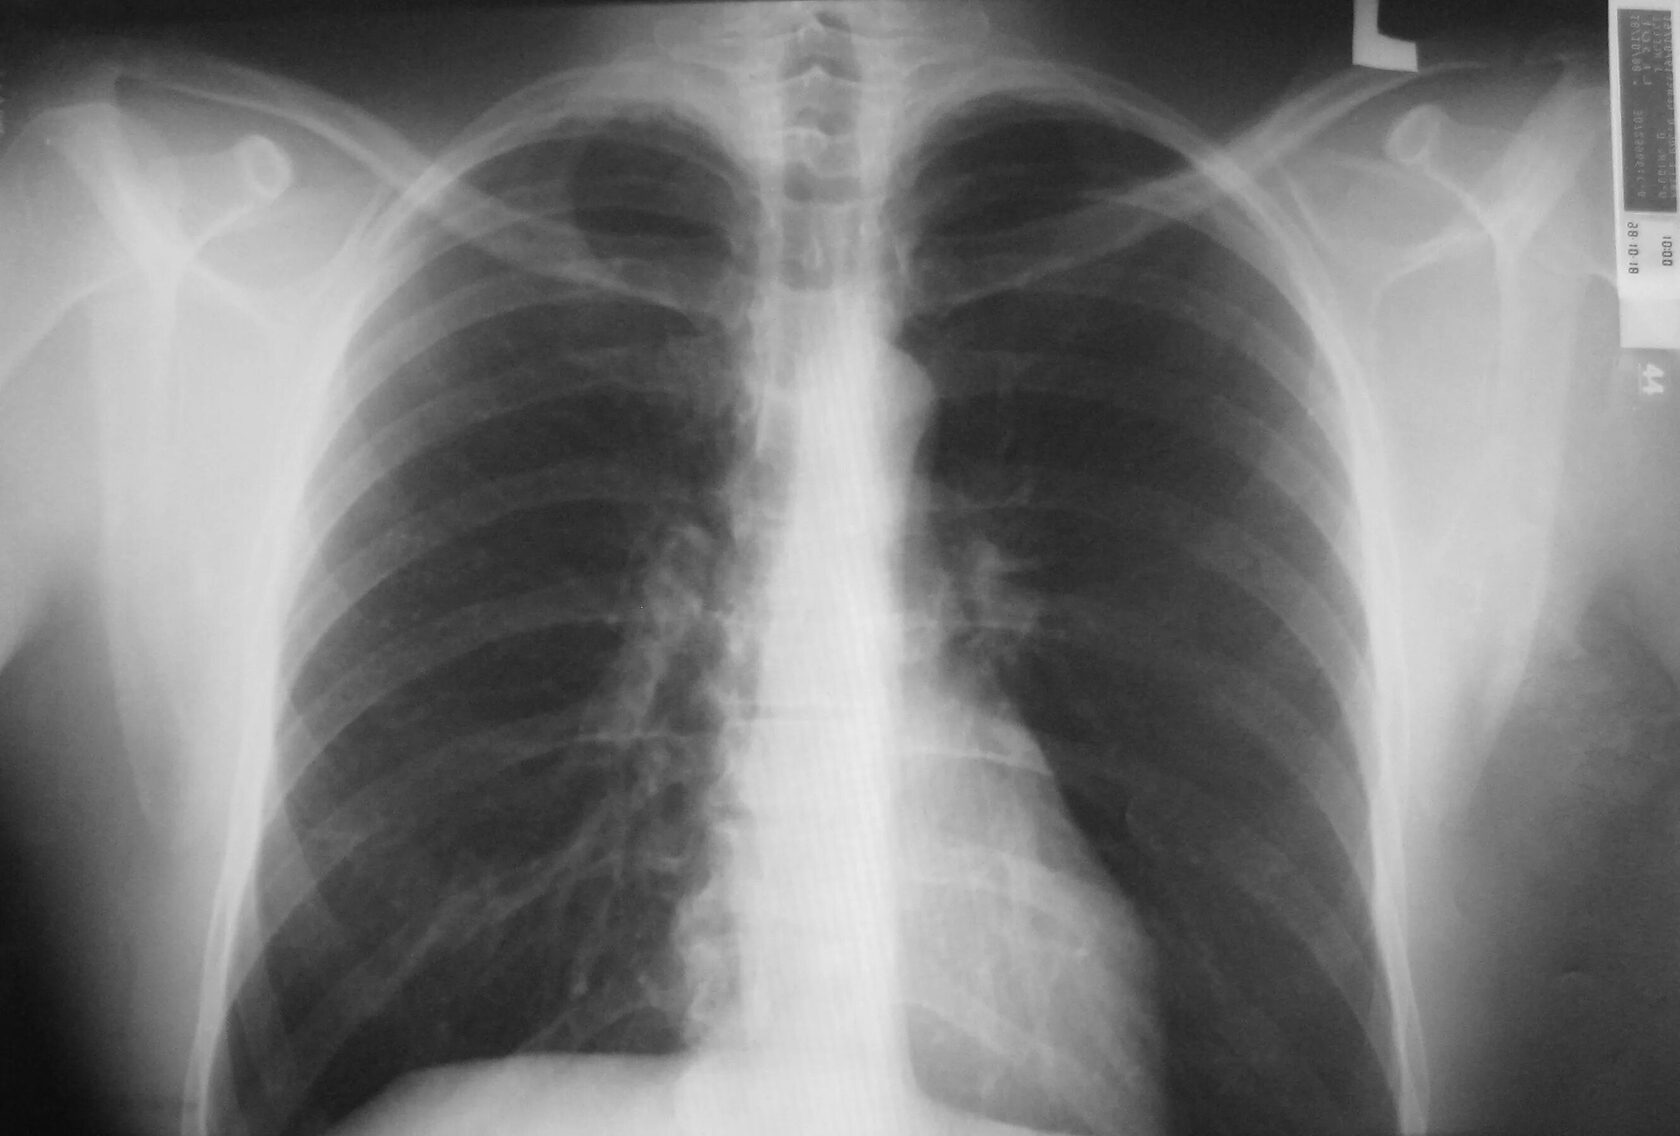

Флюорография – это одно из самых быстрых и доступных диагностических исследований, которое играет важнейшую роль в раннем выявлении серьезных заболеваний легких, в первую очередь туберкулеза и онкологических патологий. Многих пациентов волнует вопрос, сколько времени занимает сама процедура и весь процесс от начала до получения результата. Давайте подробно разберемся.

Сама процедура флюорографии занимает минимальное количество времени. Благодаря современным цифровым флюорографам, которые сегодня используются в большинстве медицинских центров, непосредственно воздействие рентгеновских лучей длится всего доли секунды.

В целом, пребывание пациента перед аппаратом, выполнение указаний медицинского персонала (задержать дыхание на несколько секунд) и получение снимка занимает не более одной-двух минут. Это делает флюорографию одной из самых быстрых диагностических процедур.